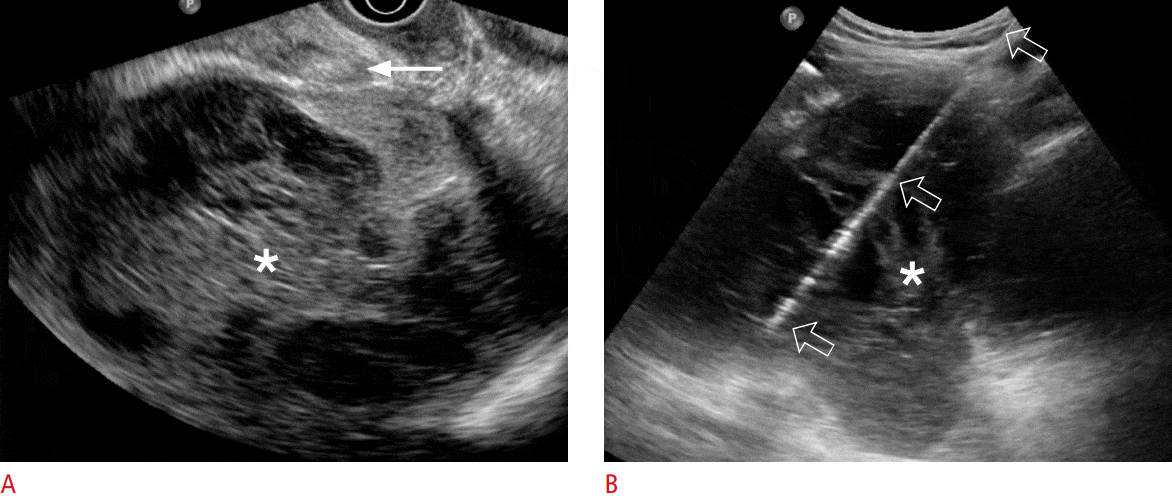

Kist evresi ileri düzeyde ise kanser gelişim olasılığı açısından sıkı takip ya da biyopsi yapılması gerekebilir. Erken evre kistlerde ise ultrason eşliğinde kist boşaltılabilir ve kist içerisine sklerozan madde verilerek kist duvarlarının birbirine yapışması sağlanır. Bu işlem genellikle klinik olarak şikayetlere yol açan ve boyutları 7-8 cm’yi bulan kistlere yönelik yapılır. Lokal anestezi altında ve ultrason eşliğinde yapılan bu işlem poliklinik ortamında kısa sürede yapılır ve sonrasında hastanede yatış gerektirmez.